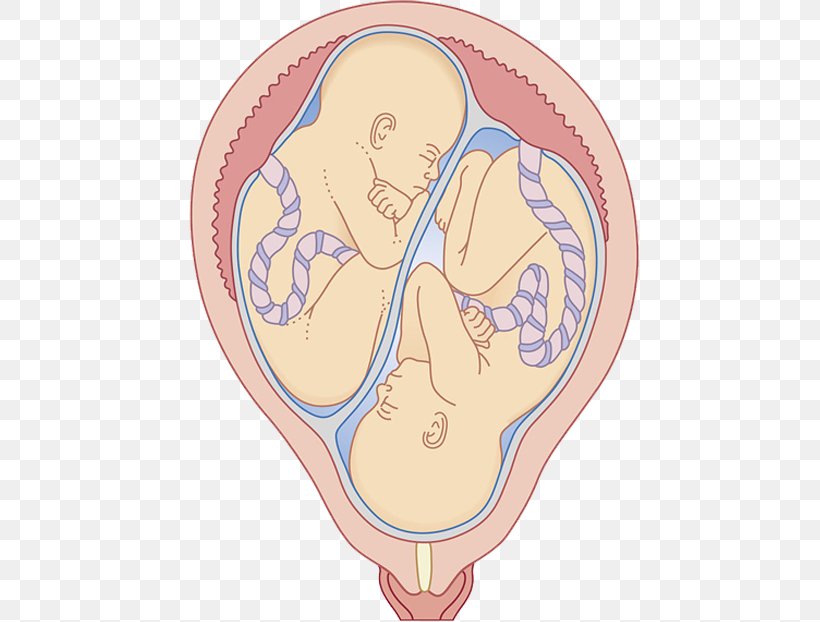

Околоплодный пузырь и плацента: структура и функции